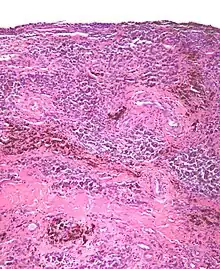

| Micrograph of diffuse TGCT, also known as pigmented villonodular synovitis. H&E stain. | |

Diffuse TGCT is sometimes referred to as pigmented villonodular synovitis (PVNS), conventional PVNS, and D-TGCT.[1]: 1 [4]: 361 [6]: 1 [2]: 102

Diffuse TGCT occurs less frequently and is locally aggressive (in some cases, tumors may infiltrate surrounding soft tissue).[3]: 245 [1]: 1 [2]: 102 [6][6]: 1 It most commonly affects people under 40 years old, though the age of occurrence varies.[2]: 102 Diffuse TGCT may occur inside a joint (intra-articular) or outside of a joint (extra-articular). Intra-articular tumors typically occur in the knee (approximately 75% of cases) and hip (approximately 15% of cases).[2]: 102 Extra-articular tumors are usually found in the knee, thigh, and foot.[2]: 101 Symptoms include swelling, pain, sensitivity, and/or limited range of motion.[2]: 102 The rate of reoccurrence is estimated to be 18-46% for intra-articular tumors and 33-50% for extra-articular tumors.[2]: 103 [6]: 1